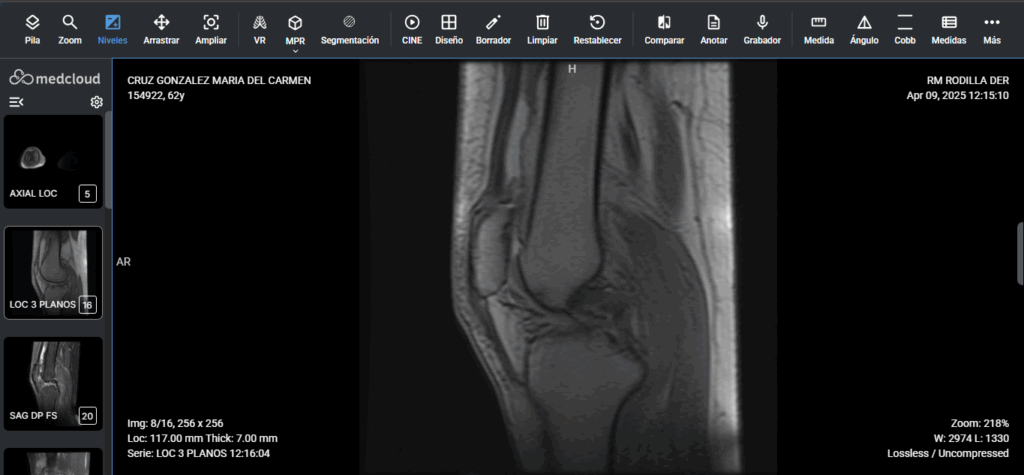

Herramientas con baja curva de aprendizaje. Su equipo se entrenó eficientemente en poco tiempo.

Con sólo unos clics y desde cualquier lugar. Trabajo de calidad y seguro en cualquier navegador de Internet.

Accede a los exámenes desde tu computadora de escritorio o usando tu computadora portátil dondequiera que estés. Acceda a informes, archivos adjuntos e imágenes en calidad original, además de todas las herramientas que necesita, dondequiera que vaya.

Calidad diagnóstica en cualquier lugar, en cualquier momento y en el menor tiempo posible.